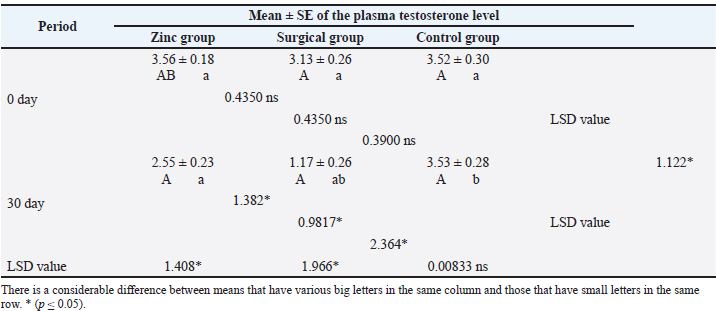

Assessment of the testicular diameterTable 2 shows the mean estimation of testicular diameters. The values of testicular diameter were dramatically (p ≤ 0.05) reduced at day 30 in the surgical group (1.48 ± 0.13) compared with the zinc gluconate group (2.49 ± 0.14) and the control group (3.10 ± 0.13) at the same period. Table 2. Testicular diameter of dogs at day 30th of the study.

Evaluation of testosterone levelsThe baseline serum testosterone concentration (Table 3) was significantly (p ≤ 0.05) declined in animals of the surgical group (1.17 ± 0.26) at day 30 than in the zinc gluconate group (2.55 ± 0.23) and control group (3.53 ± 0.28) at the same time. Conversely, there was a significant (p ≤ 0.05) decline in testosterone levels in the zinc gluconate group compared with the control group. Table 3. Evaluation of testosterone levels (ng/ml) in the treated and control groups.